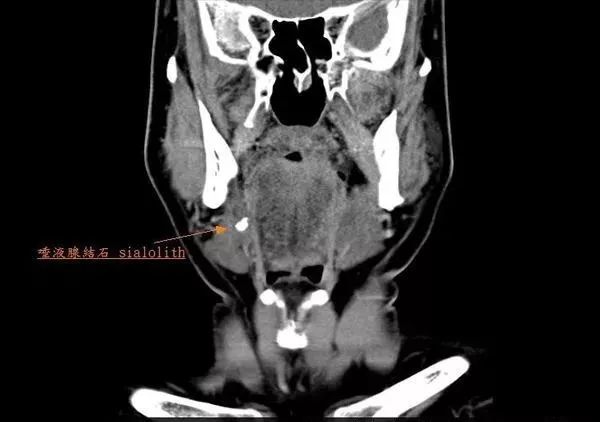

比如当导管里偶然进了异物或者生了结石的时候 , 某个通道就会变得狭窄 。 但无论通道堵成什么样 , 它们只管玩命地把口水往外送 , 从而导致堵塞 , 引起包括腮腺在内的唾液腺结石病 。

文章插图